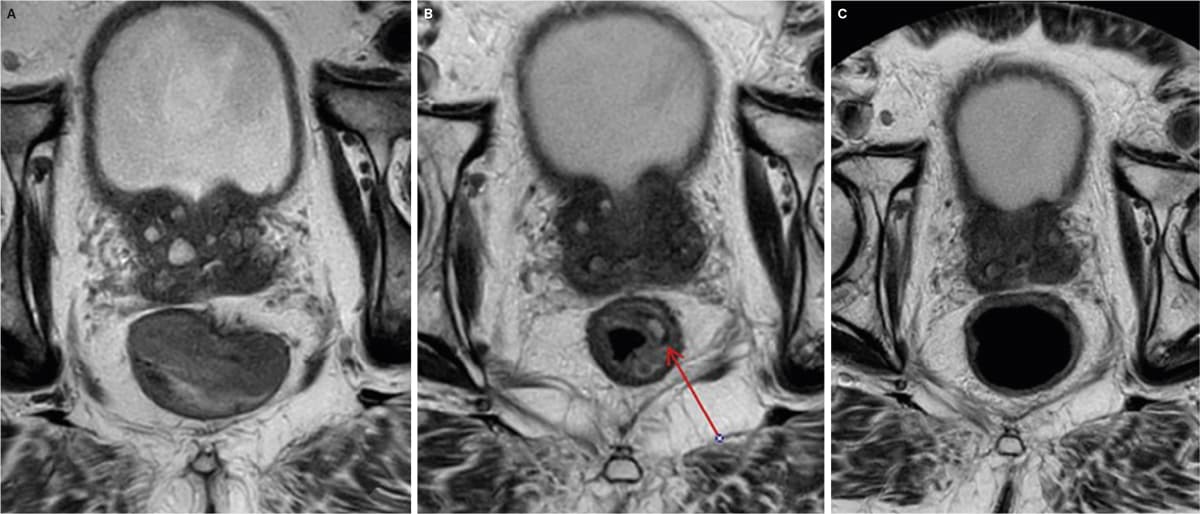

Patienten blev behandlet med radiokemoterapi efter wacthful waiting (WW)-protokollen. Efter seks uger blev der foretaget MR-skanning af rectum. På en T2-vægtet sekvens så man, at tumoren var regredieret og erstattet af fibrose med et centralt ar. Denne konfiguration kaldes split scar sign.

Kirurgi er standardbehandling af rectumcancer i Danmark, og WW udføres kun i protokolleret regi [1]. Et studie har vist, at split scar sign, et tidligt radiologisk fund, er specifikt for komplet respons [2]. Dette morfologiske tegn kan bidrage til udvælgelsen af patienter, der kan forsætte i en WW-protokol. European Society of Gastrointestinal and Abdominal Radiology anbefaler, at MR-skanning korreleres med endoskopi ved kontrol [3]. Et nyt studie har vist god livskvalitet ved lang followup på fem år [4].